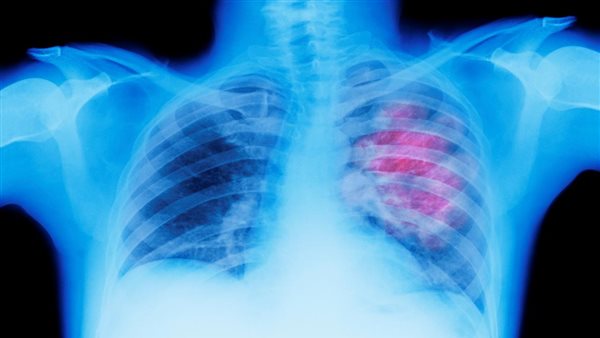

استشاري أمراض صدرية يكشف شروط التبرع بالرئة بعد الوفاة

أثارت الفنانة إلهام شاهين، الجدل على مواقع التواصل الاجتماعي، بعد أن أفصحت عن نيتها في التبرع بأعضاء جسدها بعد الوفاة، حتى يستفيد البشر منها بدلًا من أن يأكلها الدود، ووافقتها في الرأي الكاتبة فريدة الشوباشي، عضو مجلس النواب، وسط تساؤل من قبل مستخدمي مواقع التواصل، هل التبرع بالأعضاء له سن محددة؟.

من جانبه، يقول الدكتور محمود محسن، استشاري وأستاذ الأمراض الصدرية بجامعة عين شمس، إن عمليات زراعة الرئة تتم من خلال استخدام جزء من الرئة من شخص لآخر مريض.

وأضاف استشاري الأمراض الصدرية لـ القاهرة 24، أن التبرع للأعضاء يحتاج موافقة قانونية قبل أي شيء، بالإضافة إلى إجراء تحاليل للتطابق بين الشخص المتوفى والشخص المتبرع.

وتابع محسن: هناك بعض الشروط التي تتطلبها عملية زرع الرئة، وأهمها هل حالة رئة المتوفى جيدة أم لا، وألا يكون المتبرع يعاني من أمراض مزمنة، كما يفضل أن يكون السن ليس كبيرًا، فأفضل سن للتبرع هو في الفئة العمرية بين 40 إلى 50 عامًا.

وأشار أستاذ الأمراض الصدرية، إلى أنه بعد عملية النقل يحدث بعض التغييرات في حالة الرئة المنتقلة إلى الشخص حديثًا، مما يجعلها ليست بنفس قدر الكفاءة.

أما الأمراض التي تعيق عملية التبرع بالرئة، يوضح الاستشاري أن الإصابة بأورام بالرئة، أو أمراض مناعية، أو التهابات في الرئتين، كل هذه الأمراض تعيق عملية التبرع بالرئة، لذا يشترط أن تكون الرئة مؤهلة للنقل.